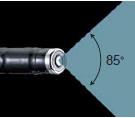

宽视场/理想长度用于观察大面积

ENF-GP具有宽85°的视野,这允许声带的高清可视化。300毫米的长度使鼻腔和咽部的观察更容易,你将能够在观察喉部时在更舒适的距离从病人工作。

光学系统 | 视野 | 85° |